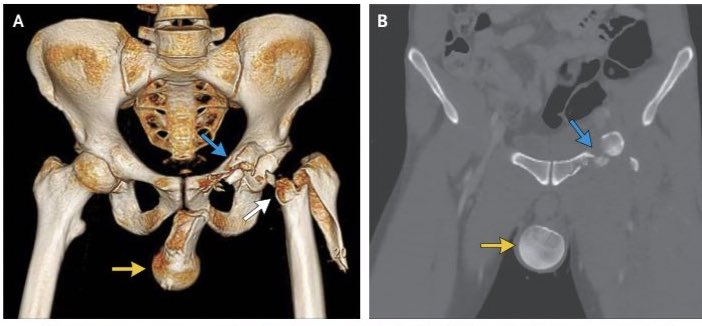

Autres clichés qui tournent à propos du tableau de bord...

Ici, ok c& #39;est un adulte (les cartilages sont fusionnés) et c& #39;est un homme (le bassin est typique)

MAIS ... c& #39;est un accident de moto.

Ici, ok c& #39;est un adulte (les cartilages sont fusionnés) et c& #39;est un homme (le bassin est typique)

MAIS ... c& #39;est un accident de moto.